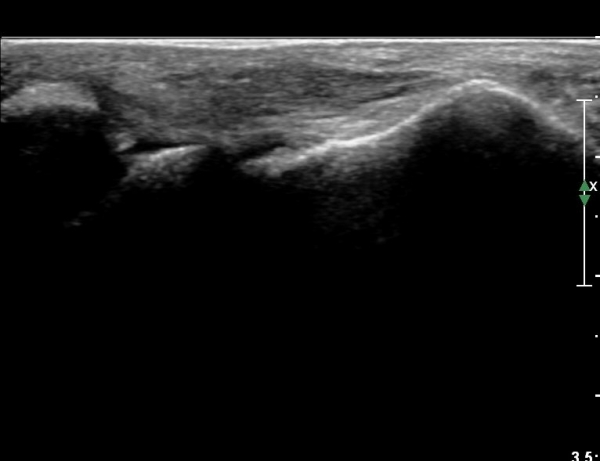

Àü°ÅºñÀÎ´ë ºÎÇϰ˻翡¼­ ÀδëÆÄ¿­ ºÎÀ§°¡ ¹ú¾îÁö°í °Å°ñÀÌ ¾ÕÀ¸·Î ´Ü°ÜÁö´Â ¼Ò°ßÀ» º¸ÀÓ(»çÁø 3, 4, ÷ºÎ µ¿¿µ»ó).